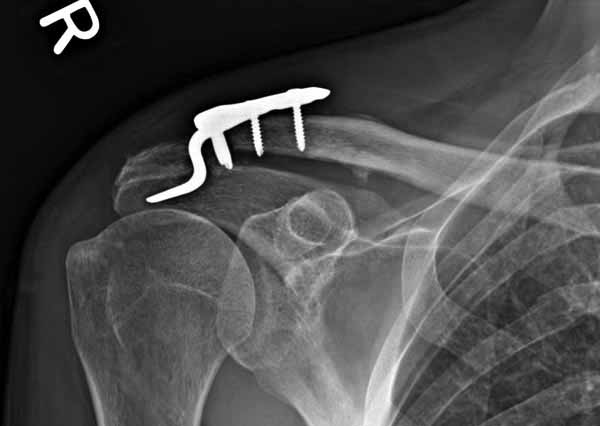

1.JPG

60KB (62415 bytes)

|

Отправитель: Серж 24 Июнь 2011, 13:41

foto

2.JPG

12KB (12589 bytes)

Re: ключичная пластинка

Отправитель: Серж 24 Июнь 2011, 13:42

foto 3

3.JPG

14KB (15209 bytes)

Отправитель: Серж 24 Июнь 2011, 13:43

foto 4

4.JPG

14KB (14434 bytes)

Отправитель: Серж 24 Июнь 2011, 13:45

foto 5

коллаж у меня не получился, пришлось отдельно рентгенограммы присоединить :-))

5.JPG

15KB (16356 bytes)

Замечание понял, спасибо и нормальные рентгенограммы, молодец!

Во вторых, это хорошо что нашли длинную пластину, я об этом писал "пластина короткая, не покрывает медиальный диафизарный фрагмент ключицы", и у нас не получилось, пластина не выдержала...

Мне кажется что если понять принципы, то можно использовать и короткую пластину. Что мы с успехом применяли раньше и применяем сейчас, но уже более осознанно. В вашем случае Серж, у меня стойкое ощущение, что необходима дополнительная иммобилизация, так как неправильно выбрано место введения крючка и при ранней нагрузке пластину просто вырвет. Если вам несложно не могли бы вы продемонстрировать прямую и боковую проекцию и в более хорошем качестве. ИМХО

Теоретически можно использовать и короткую пластину. Но на операции дистальный отломок( акромиальный конец ключицы ) был коротким и оскольчатым, поэтому крючок и использование там блокированных винтов в пластине было очень уместно. Доступ - "сабельный удар". Точка введения крючка - сразу сзади от ключично-акромиального сустава. Если честно - больше внимания уделяли репозиции отломков и адекватному расположению пластины на ключице :-) крючок проверяли на прочность фиксации за акромион и полный объем движений в плечевом суставе. После операции рука на косынке, нагрузку ограничили. Снимки есть в нормальном разрешении, но здесь "размер файла не превышал 75 кб." Если есть необходимость залью в пикассу...